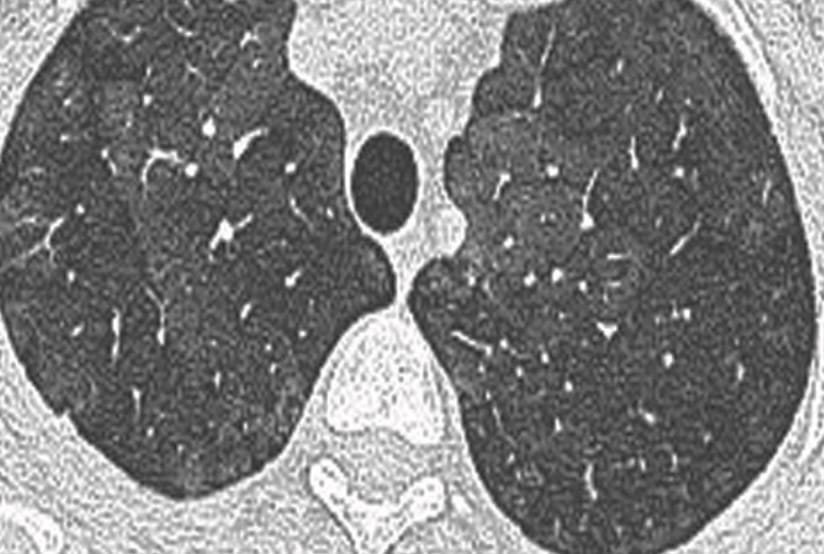

• Alveolar [Smoker’s] Macrophage Pneumonia (AMP) replaces Desquamative Interstitial Pneumonia

Yes, we cannot tell how much of the opacity is SRIF versus Smoker’s Macrophages versus both!

Suggested reporting terminology

“Findings of Smoker’s Lung are present in the form of: centrilobular emphysema in the upper lungs and patchy pulmonary ground glass opacities, consistent with accumulation of Smoker’s Macrophages and, possibly, Smoking-Related Interstitial Fibrosis.”